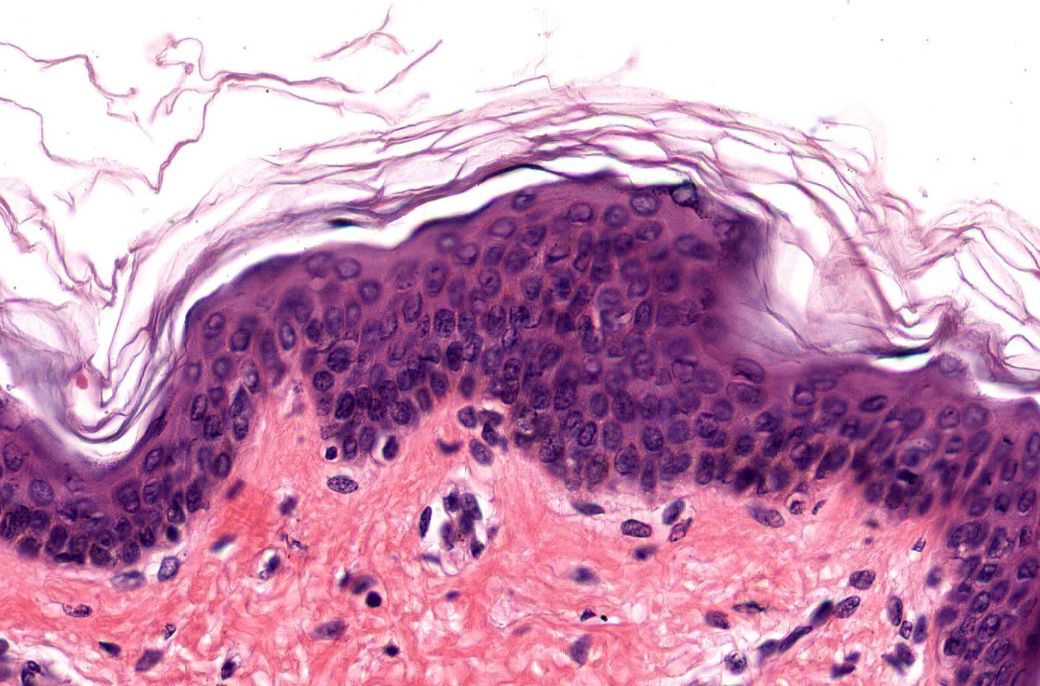

Piel Delgada

Piel Gruesa